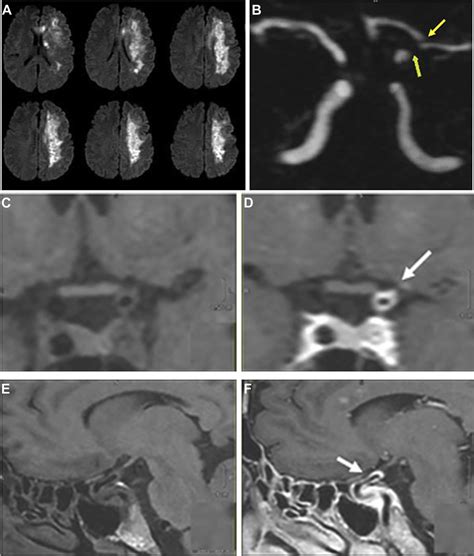

• Computed Tomography (CT) Scan: This is often the first imaging test performed in the emergency room setting for suspected stroke. A CT scan uses X-rays to create cross-sectional images of the brain. It’s excellent at quickly ruling out a hemorrhagic stroke , which is super important. While a standard non-contrast CT might not show the ischemic changes immediately (especially in the early hours), it can reveal signs of early ischemia like subtle loss of gray-white matter differentiation or a hyperdense artery (indicating a clot). Contrast-enhanced CT, like a CT angiography (CTA), is incredibly useful for visualizing the blood vessels and identifying the location of the clot or stenosis causing the ischemic event. CTA can show us where the blockage is and give us an idea of the vessel’s condition.

• Magnetic Resonance Imaging (MRI): MRI uses powerful magnets and radio waves to generate highly detailed images of the brain. It’s generally considered more sensitive than CT for detecting acute ischemic stroke, especially in the early stages. Different MRI sequences provide a wealth of information . For instance, diffusion-weighted imaging (DWI) is incredibly sensitive to the cytotoxic edema that occurs within minutes of an ischemic event, allowing for very early detection of infarction. Perfusion-weighted imaging (PWI) can assess blood flow through the brain tissue, helping to identify areas of compromised perfusion that might be salvageable. MRI angiography (MRA) is another technique used to visualize the blood vessels, similar to CTA but without the ionizing radiation. While MRI offers superior detail, it takes longer than a CT scan and may not be readily available in all emergency settings, and patients with certain implants might not be able to undergo the scan.

• Cerebral Angiography (DSA): Digital subtraction angiography is considered the gold standard for visualizing the cerebral vasculature. It involves inserting a catheter into an artery (usually in the groin) and guiding it up to the arteries in the brain, injecting contrast dye directly into the vessels. This provides extremely detailed, real-time images of blood flow and can precisely pinpoint blockages. DSA is typically reserved for cases where more information is needed before or during intervention , such as mechanical thrombectomy (clot removal). It’s highly invasive compared to CT or MRI, but it offers unparalleled detail and allows for immediate therapeutic intervention.